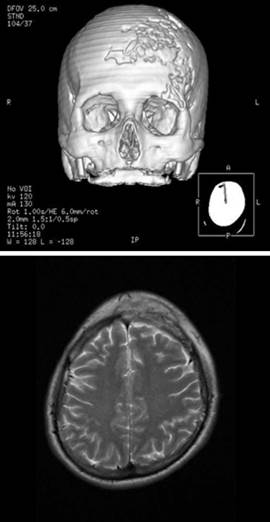

On physical examination, he presented with growth of the right frontal region, without the presence of dermatological lesions, lymph-adenopathy or visceromegaly. Complementary laboratory tests (complete blood count, blood chemistry, sedimentation rate, C-reactive protein, proteinogram, immunoglobulins, complement, ANA, VDRL, hepatitis and HIV, beta-2-microglobulin and chest radiography) were performed, which were normal or negative. Initial imaging studies showed extensive inflammatory/infectious bone involvement, which led to suspect osteomyelitis as the first diagnostic possibility (Figure 1).

Figure 1 Initial imaging studies of the lesion showing extensive inflammatory bone involvement, with osteomyelitis as the first diagnostic possibility.